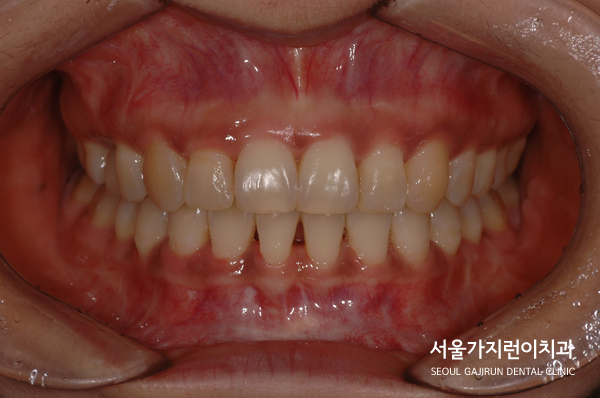

오늘은 과개교합 환자의 교정 케이스를 가져와봤습니다.

과개교합이란, 상악의 치아가 하악의 치아를 비정상적으로 덮은 교합 상태를 말합니다.

정면에서 봤을 때 윗니가 아랫니를 덮어 전혀 보이지 않는 상태였죠.

그래서 환자 분의 경우 기능적인 문제개선을 위해 교정치료를 진행했는데요.